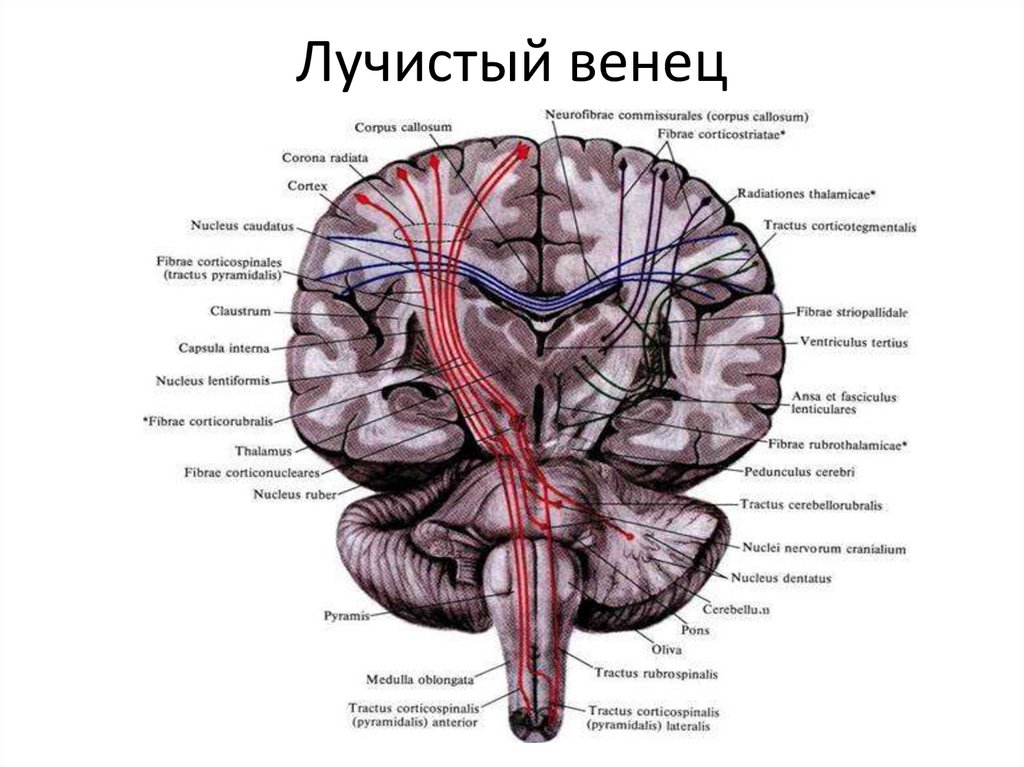

Анатомия: Задняя соединительная артерия мозга